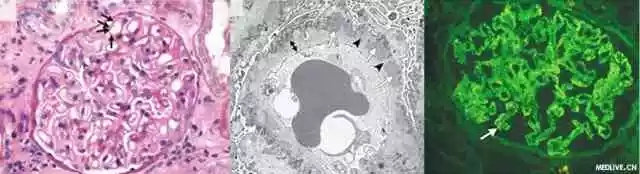

该品是生化试剂,也是医学诊断药物,主要用于荧光抗体技术中的荧光染料,能和各种抗体蛋白结合,结合后的抗体不丧失与一定抗原结合的特异性。并在碱性溶液中具有强烈的绿色荧光

其大发射光波长为520~530nm,呈现明亮的黄绿色。fitc在冷暗干燥处可保存多年,是目前应用广泛的荧光素。其主要优点是人眼对黄绿色较为敏感,通常切片标本中的绿色荧光少于红色。